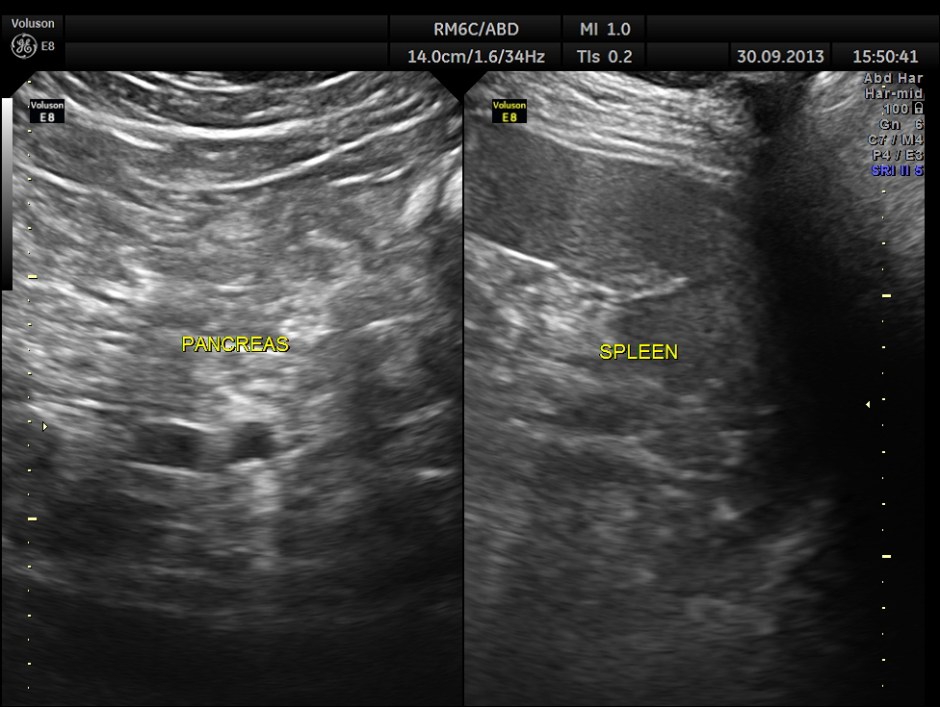

This was a 57 year old gentleman , with complaints of difficulty in passing urine and dysuria of 1 month duration.

His upper abdominal scan was normal . His left kidney was normal.